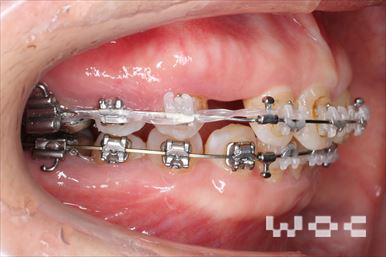

上下舌側矯正を希望。上顎両側第一小臼歯の抜歯としたが上顎右側第二小臼歯は治療した歯であったため、抜歯部位を変更。治療の難度が上がったため治療期間が少し延長しました。

- 年齢:33歳女性

- 主訴:出っ歯、前歯で噛めない

- 基本矯正料金:1,295,000円

- 治療期間:2年8ヶ月

- 抜歯部位:上顎右側第二小臼歯、左側第一小臼歯